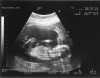

Nu har vi sett våran bäbis! Var på ultraljud idag och fick med oss tre stycken foton på vår inte riktigt färdiga bäbis. tufft va? Sandman hade ju självklart med sig sin nyinförskaffade digitalkamera och tog lite bilder, ett par återfinns i arkivet minsann!